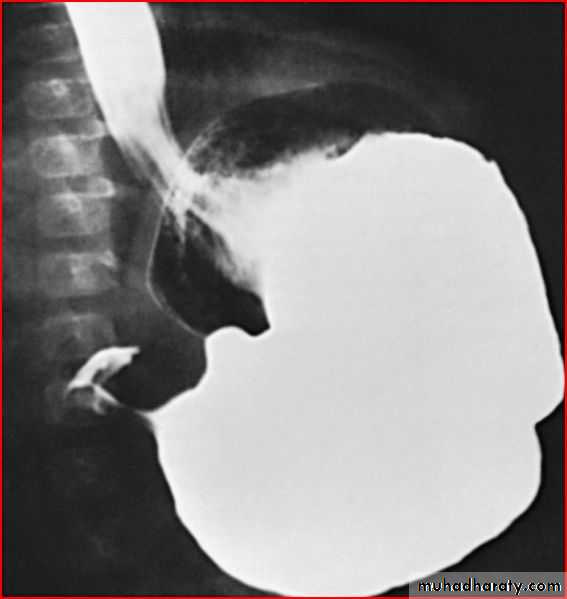

Barium meal showing pyloric stenosis

Esophagial atresia or achalasia ???